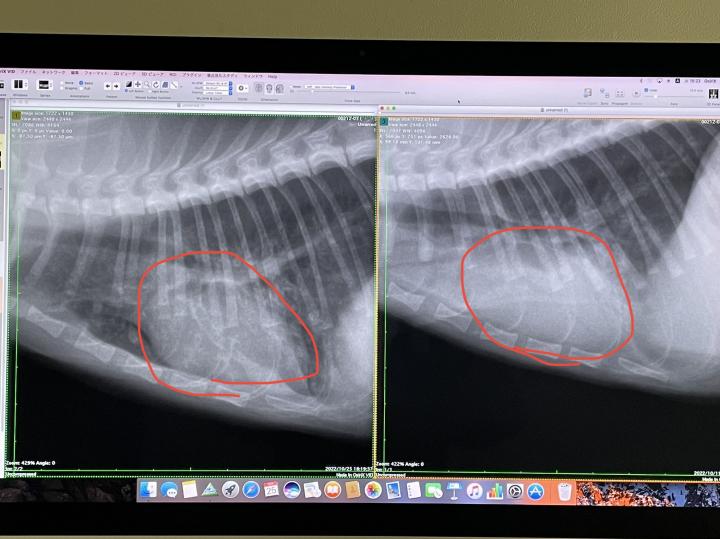

右退院時

左火曜日

赤マルの中の心臓の形がはっきり見えるようになりました